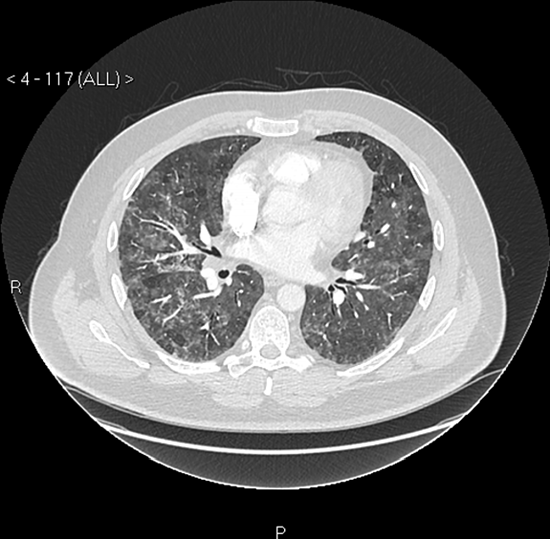

Kết quả chụp CT lồng ngực của Martin Taylor. Ảnh: BMJ

Martin Taylor, 43 tuổi, người đàn ông Scotland được chẩn đoán mắc bệnh viêm phổi do sử dụng chăn lông vũ.

Trường hợp của Martin được báo cáo trên British Medical Journal ngày 18/11. Ban đầu, các biểu hiện của anh gồm có khó thở và choáng váng khi hoạt động. Hai tháng sau triệu chứng, anh gặp khó khăn khi đi lại và thường xuyên cảm thấy như sắp ngất đi.

Tuy nhiên, sau khi phân tích công thức máu của anh, bác sĩ Owen John Dempsey, chuyên khoa Lồng ngực tại Bệnh viện BMI Albyn ở Aberdeen, Scotland nhận ra, căn bệnh bắt nguồn từ việc sử dụng chăn lông vũ. Hệ thống miễn dịch của anh có dấu hiệu tiếp xúc với các protein từ gia cầm. Martin được chẩn đoán mắc viêm phổi quá mẫn, hậu quả của hen suyễn dị ứng. Nếu phát hiện sớm, bệnh dễ điều trị. Tuy nhiên không được chẩn đóan kịp thời, bệnh có thể dẫn đến xơ phổi vĩnh viễn, thậm chí tử vong.